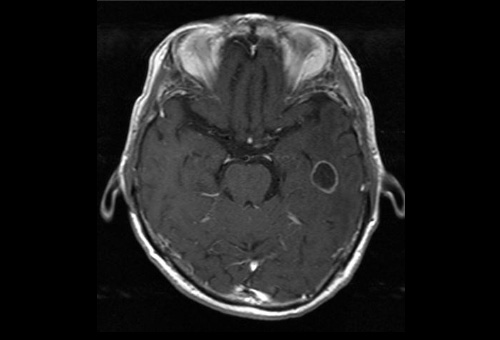

乳癌からの転移

治療前

治療一ヶ月後 腫瘍、浮腫の消失